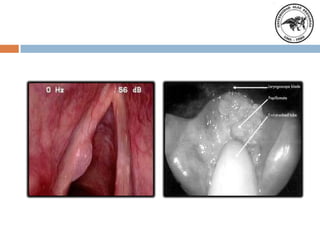

Diagnostico

Historia clínica, profesores,

locutores, cantantes, personas

que gritan. Laringoscopia

indirecta y directa.

Estroboscopia.

Videolaringoscopia

Tratamiento quirúrgico

Microcirugía laríngea, visión

directa, anestesia general.

Laser dióxido de carbono.

Microcirugía asociada al

laser.

Granuloma

Localización

Es un pseudomotor de

laringe producido por un

trauma continuo. Se

sitúa en tercio posterior

a nivel de la apófisis

vocal del cartílago

aritenoides

Clínicamente por

antecedentes de

intubación reflujo

gastroesofágico.

Laringoscopia indirecta.

Fibroscopia

Microcirugía endolaringea. Laser

dióxido de carbono. Evitar la

lesión de la superficie

cartilaginosa